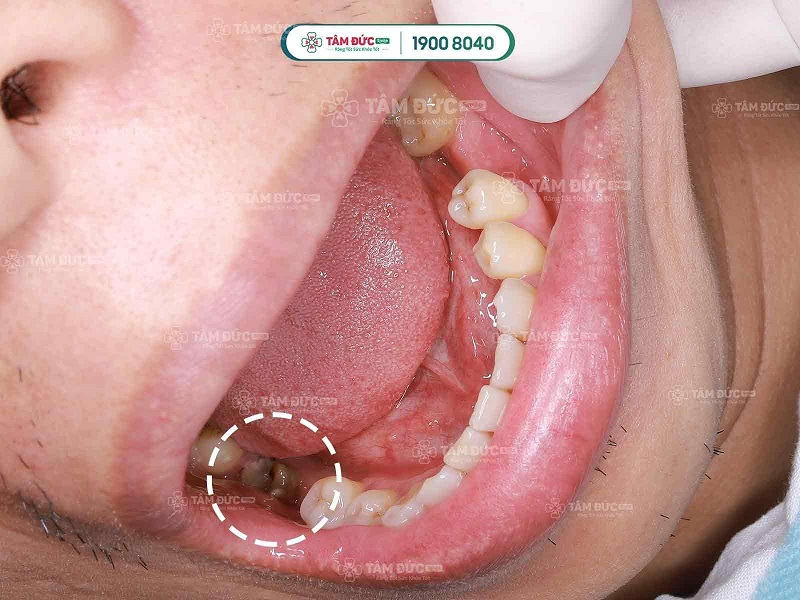

2.2 Nguyên nhân phổ biến

- Sâu răng nặng: Mảng bám và vi khuẩn phá hủy men răng, lan đến ngà và tủy.

- Răng mẻ, vỡ do chấn thương: Tạo điều kiện cho vi khuẩn xâm nhập.